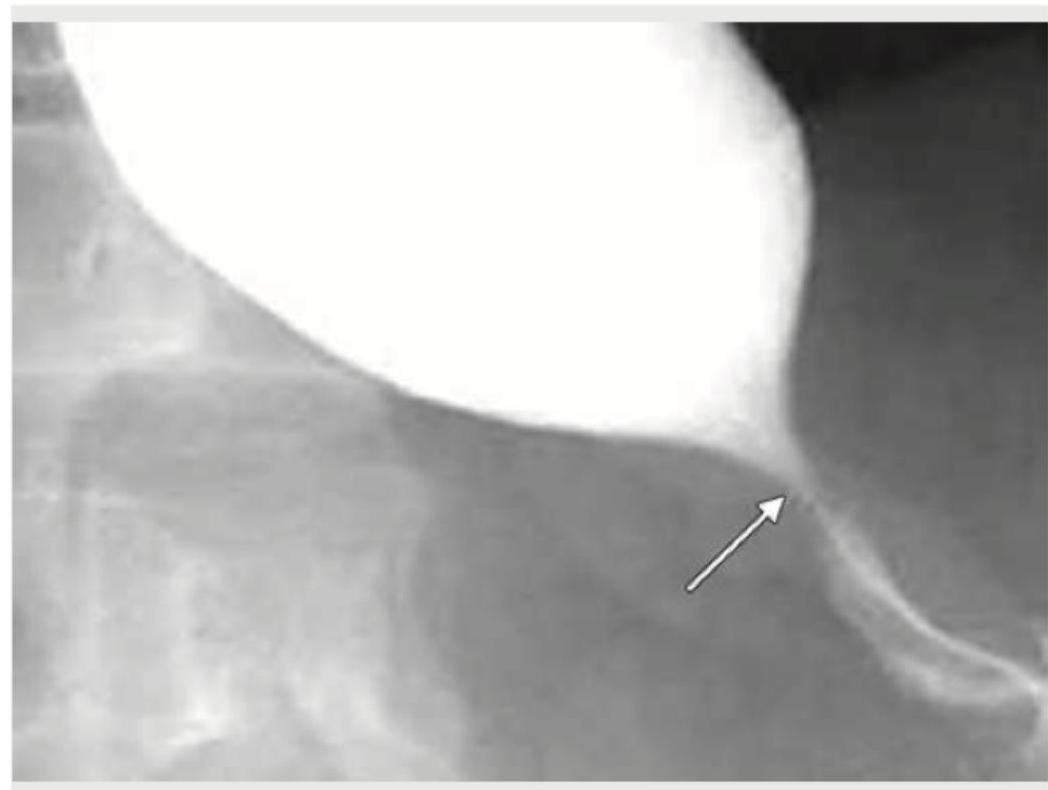

A 35-year-old woman presents with progressive dysphagia to solids. A barium swallow study is performed. Which of the following is true regarding the condition shown in the image?

Explanation: ***Associated with iron deficiency anemia*** - The image shows an **esophageal web** in the upper esophagus, characteristic of **Plummer-Vinson syndrome** (also known as **Paterson-Brown-Kelly syndrome**). - This syndrome consists of the classic triad: **iron deficiency anemia**, **dysphagia**, and **esophageal webs**. - The webs are thin membranes of tissue in the upper esophagus that cause intermittent dysphagia to solids. - Treatment involves **iron supplementation** and mechanical dilation of the web if symptomatic. - This is a **premalignant condition** with increased risk of **post-cricoid and upper esophageal squamous cell carcinoma**. *Increased tone of lower esophageal sphincter* - Increased tone of the **lower esophageal sphincter** is characteristic of **achalasia**, which presents with a **"bird's beak" appearance** on barium swallow. - Achalasia is a primary **motility disorder** caused by degeneration of the myenteric plexus, not a structural web. - The image shows a **web in the upper esophagus**, not LES pathology. *Not a premalignant condition* - Esophageal webs, particularly in **Plummer-Vinson syndrome**, are considered a **premalignant condition**. - There is increased risk of developing **squamous cell carcinoma** of the post-cricoid region and upper esophagus. - Regular **endoscopic surveillance** is recommended due to this malignant potential. *It is a normal phenomenon* - The presence of an **esophageal web** is an **abnormal anatomical structure** and pathological finding. - Esophageal webs cause **dysphagia** and are associated with underlying conditions like **iron deficiency anemia**. - Normal esophageal mucosa should be smooth without web-like strictures.